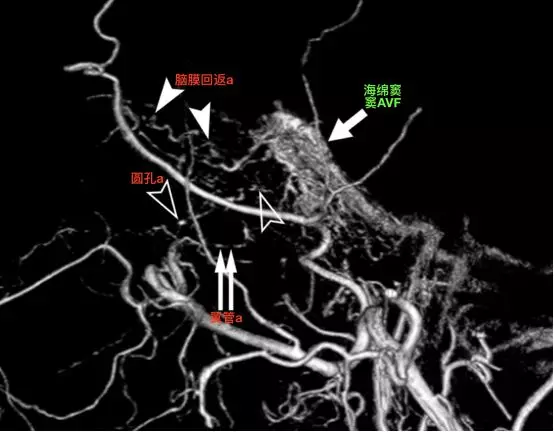

术前造影,脑动静脉畸形之前已部分栓塞。椎动脉造影的侧位(A)和正位(B)显示双侧小脑半球的巨大脑动静脉畸形,有多量供血来自后循环。虚线四边形表示三叉神经的大致位置。

A-B,左侧颈外动脉的侧位和正位。迂曲的脑膜中动脉(直箭)和圆孔动脉(箭头),均供应畸形血管团(Levitt 2011)。